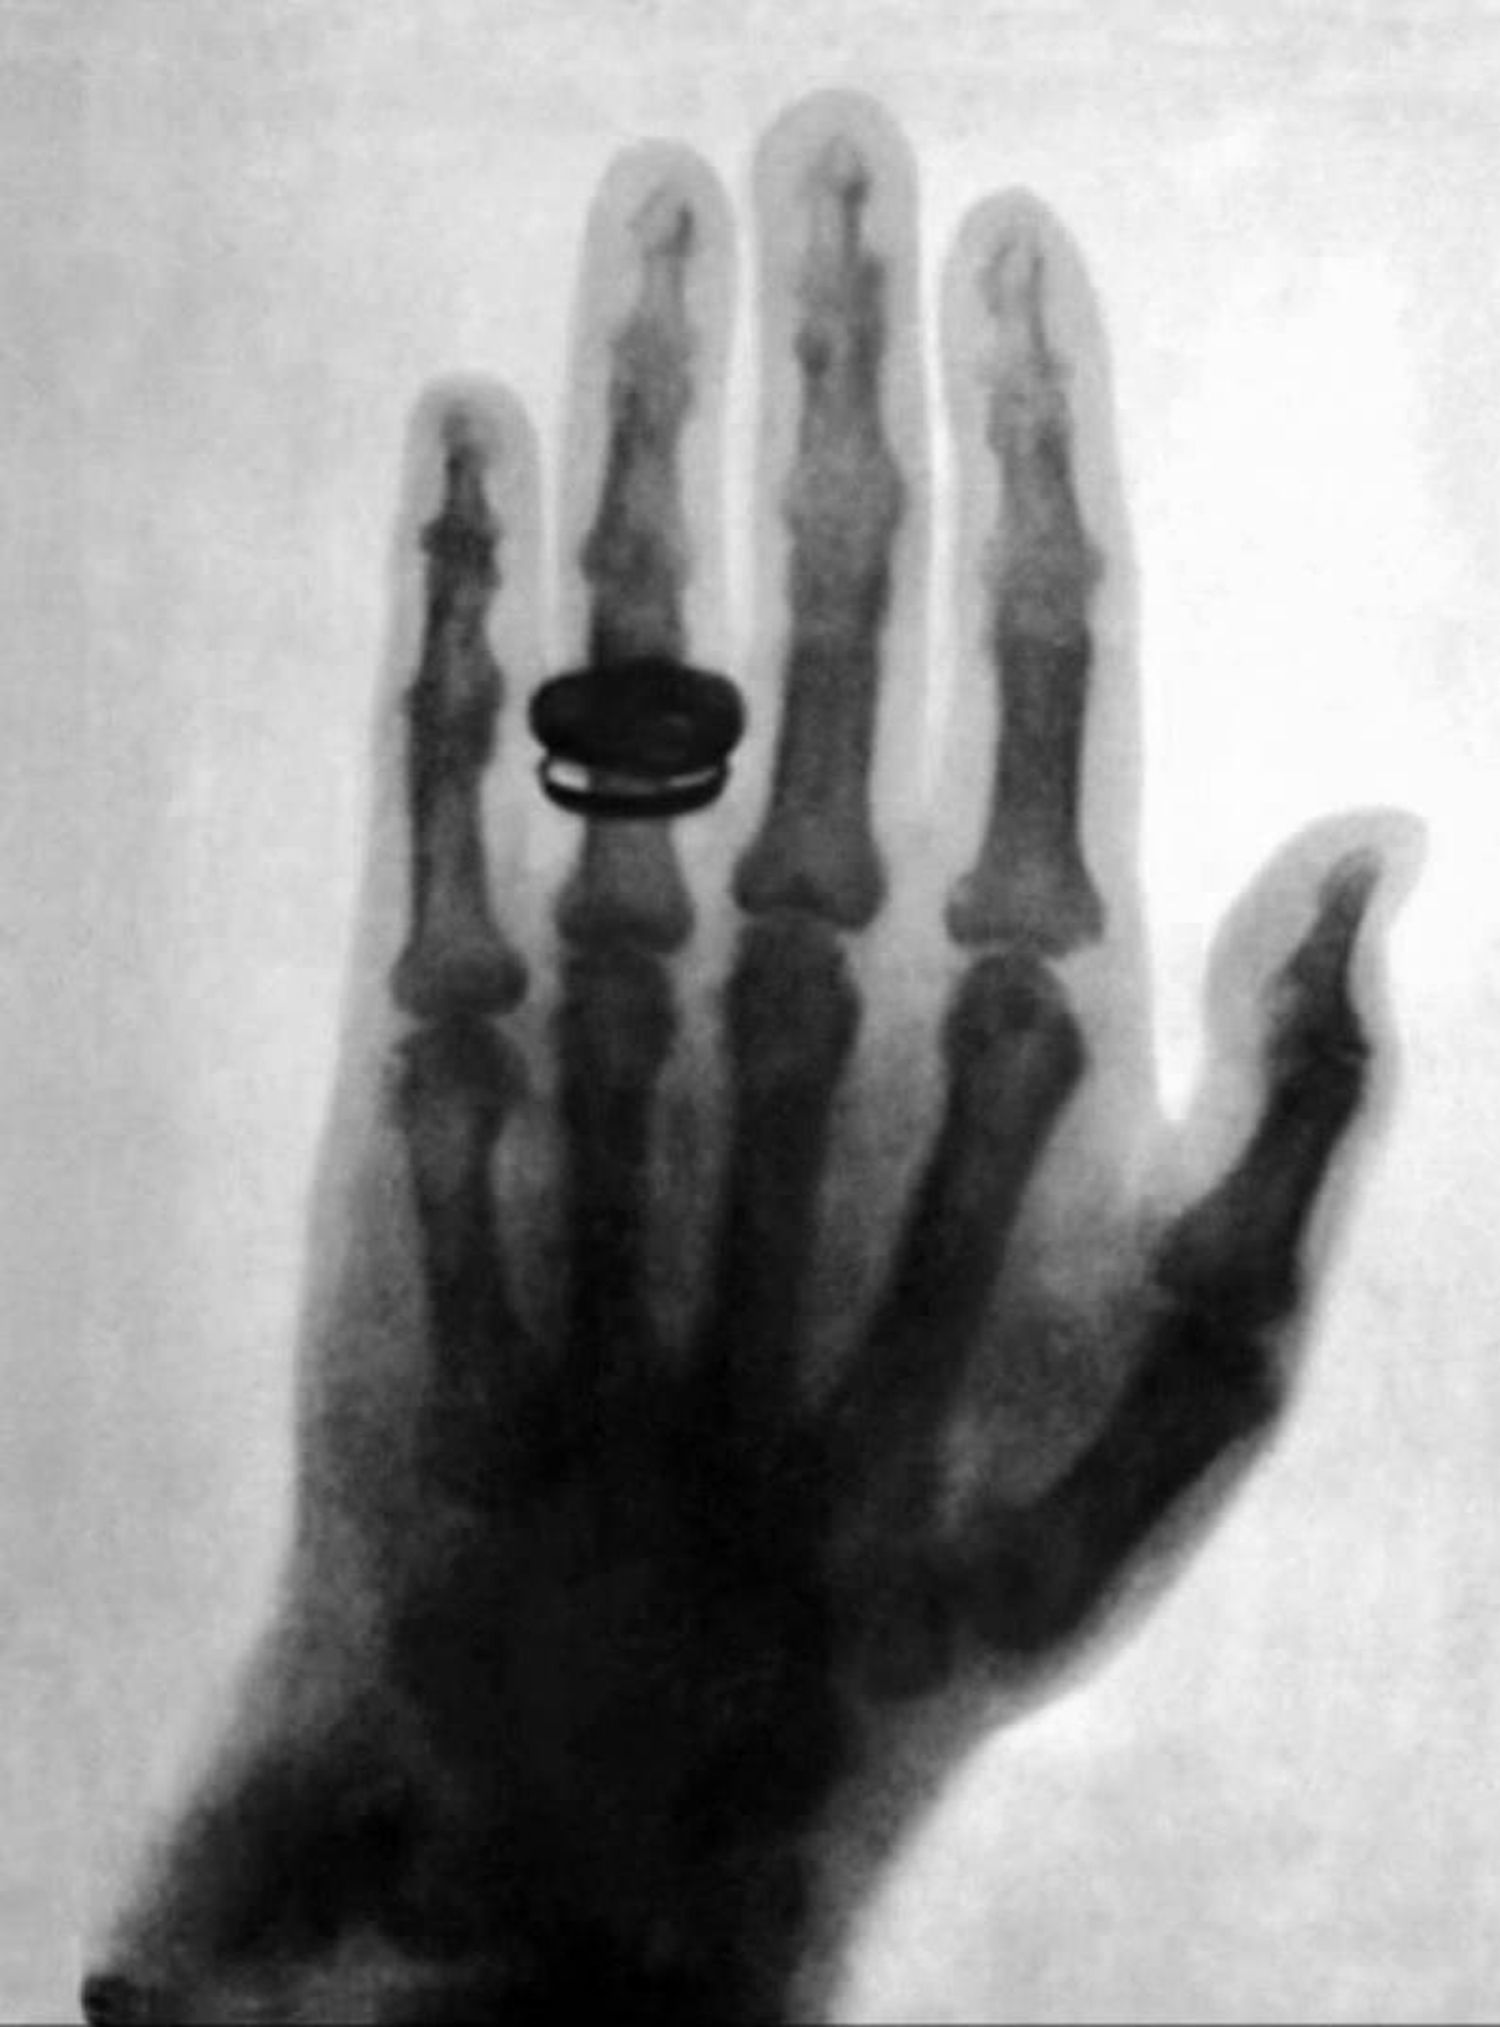

二、解剖学家阿尔伯特·冯·科利克于 1896-01-23 获得的手X光片

Radiografía de la mano del anatomista Albert von Kölliker obtenida por el mismo Röntgen el 23 de enero de 1896.

解剖学家阿尔伯特·冯·科利克于 1896-01-23 获得的手X光片。

Albert von Kölliker, influential anatomist and physiologist and a close friend of Roentgen. He proposed that X-rays be called Roentgen Rays.

阿尔伯特·冯·科利克,有影响力的解剖学家和生理学家,伦琴的密友。他建议将X射线称为伦琴射线。

Fig. 2 Left: X-ray of Anna Bertrand Röntgen’s hand (1895-12-22). Right: X-ray of Albert von Kölliker’s hand (1896-01-23).

Left: X-ray of Anna Bertrand Röntgen's hand (1895-12-22). Right: X-ray of Albert von Kölliker's hand (1896-01-23).

左图:安娜·柏莎·伦琴的手部X光片(1895-12-22)。右图:阿尔伯特·冯·Kölliker手部的X光片(1896-01-23)。